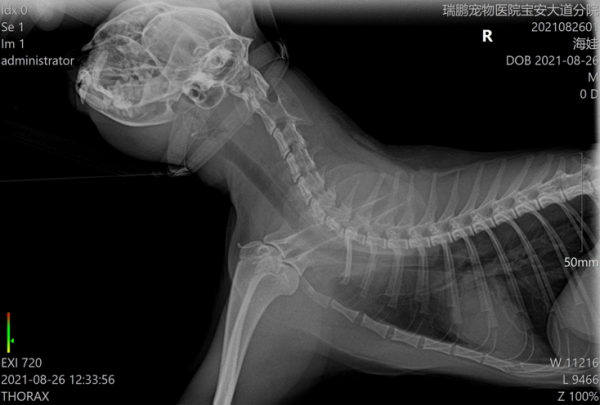

鍾醫生立馬為喵喵做了一系列細緻的檢查,包括血常規、SAA、穿刺細胞學檢查、影像學檢查(超聲波檢查和X光檢查)等。

影像學檢查:包括超聲波檢查和X光,只要給喵“照一照”,就能知道喵身體內部情況。